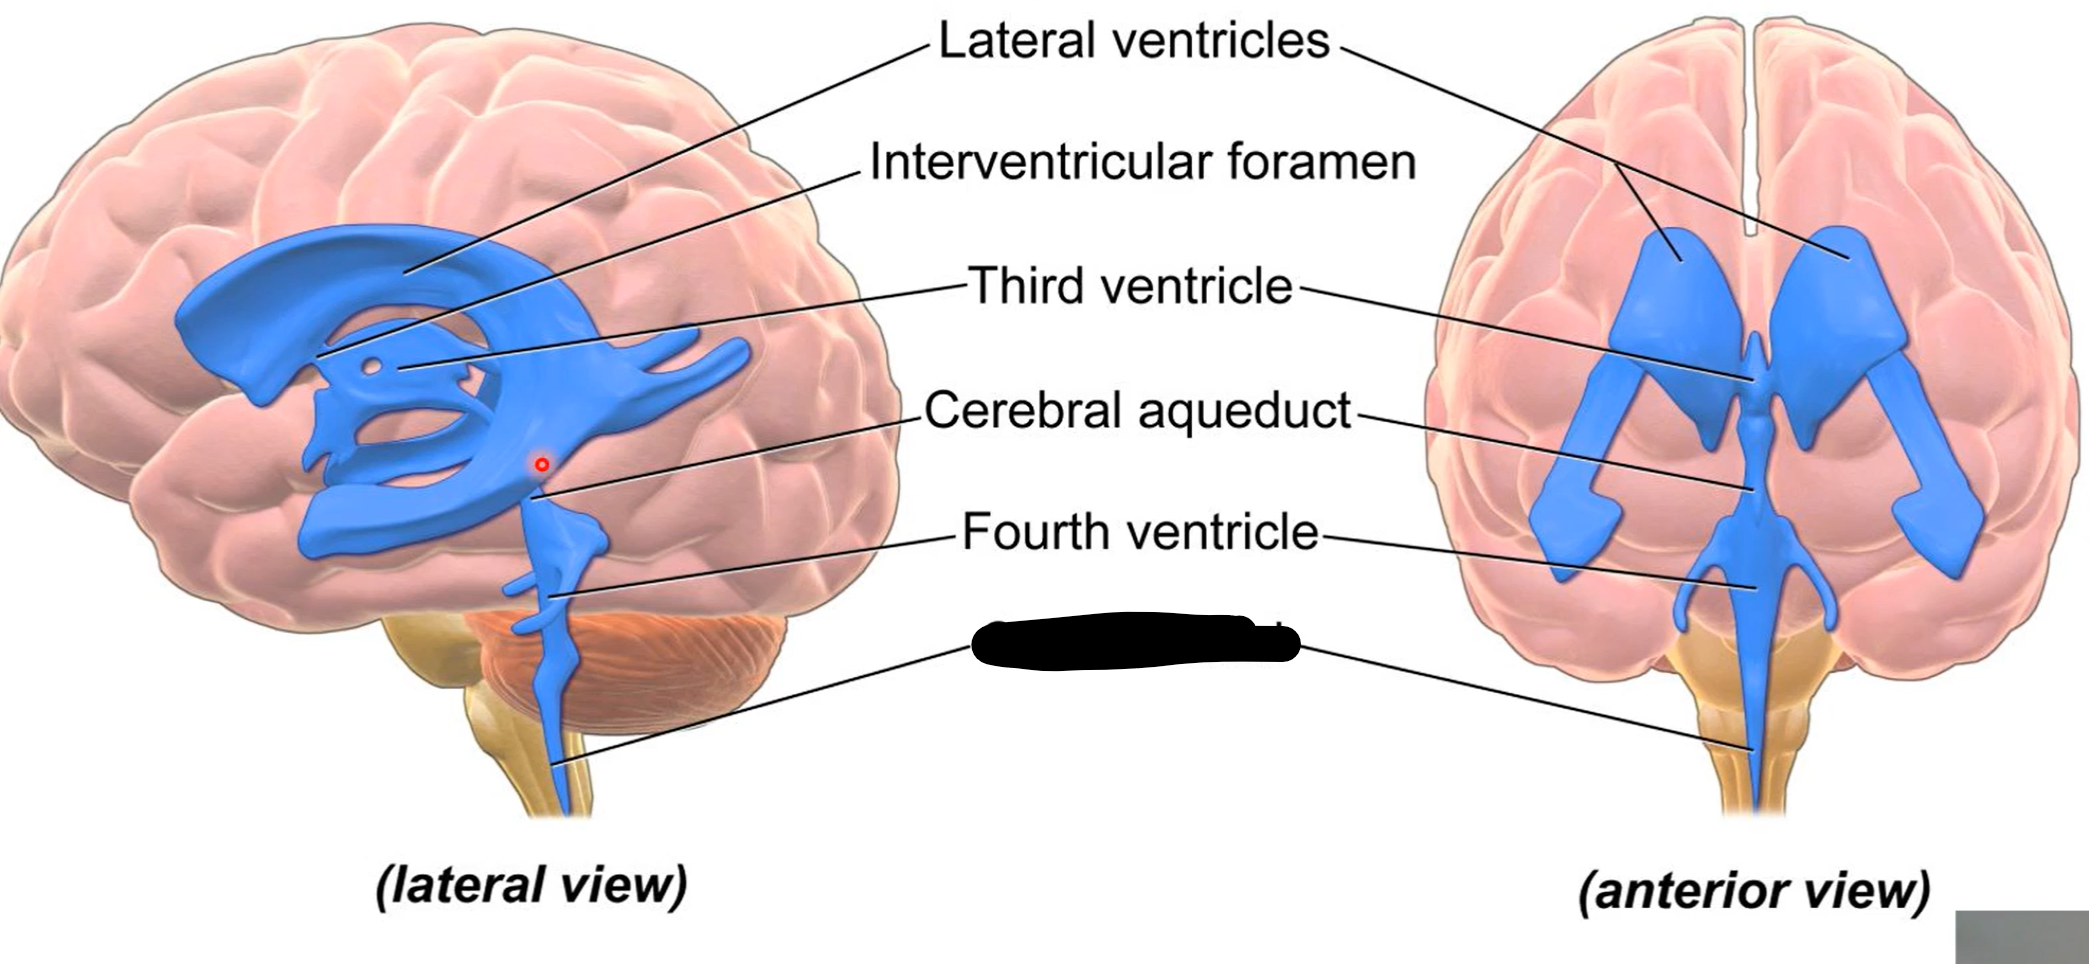

What do brain ventricles contain?

CSF

What makes CSF?

Choroid plexus

Where does CSF go from ventricles?

Subarachnoid space to enter circulation via arachnoid granulations

Choroid plexus

What carries CSF from 4th ventricle to subarachnoid space?

Median and lateral apertures

Arachnoid granulations

Lateral ventricles

Interventricular foramen

Third ventricle

Cerebral aqueduct

Fourth ventricle

Central canal